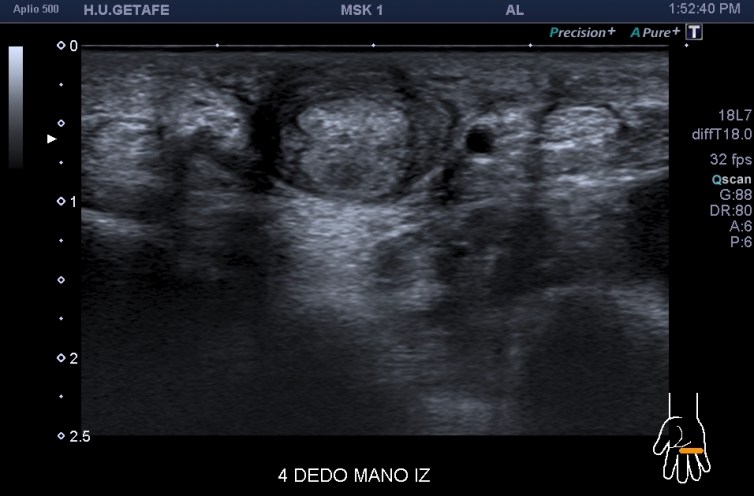

En la imagen 2 la imagen resulta fantástica, detente a estudiarla, coexiste normalidad del 5to dedo en eje corto y el 4to dedo afectado por una inflamación en su vaina que lo envuelve como una circunferencia marcando la anatomía de ambos flexores manera increíble. La imagen 3 es para que disfrutes de la anatomía sin letreros, es espectacular.